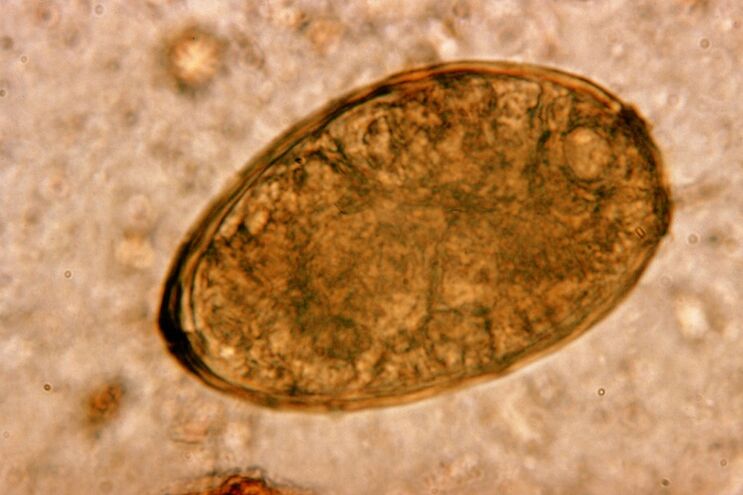

The fluke lives in the lungs in pairs, forming cysts in the bronchi.Infestation occurs by eating crabs and crabs infected with the parasite.Once in the gastrointestinal tract, the pulmonary fluke penetrates the peritoneum and reaches the lungs through the diaphragm, causing a persistent cough in the patient.

The small helminth lung parasite, belonging to the class of trematodes, “specializes” in parasitizing specifically in the lungs.It causes much more serious problems in the respiratory system than, for example, intestinal worms.

At the site of their localization, infiltrates appear and hemorrhages develop, as a result of which cavities appear filled with decomposing metabolites of worms, dead parasites and lung tissue.The damage caused by the lung fluke is further compounded by the fact that it has a long liver and can live in the host's body for up to 20 years.